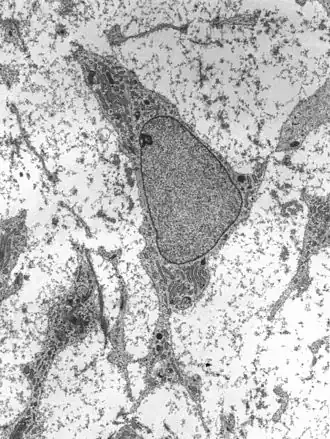

![]() Просвечивающая электронная микрофотография мезенхимальной стволовой клетки, показывающая типичные ультраструктурные характеристики | |